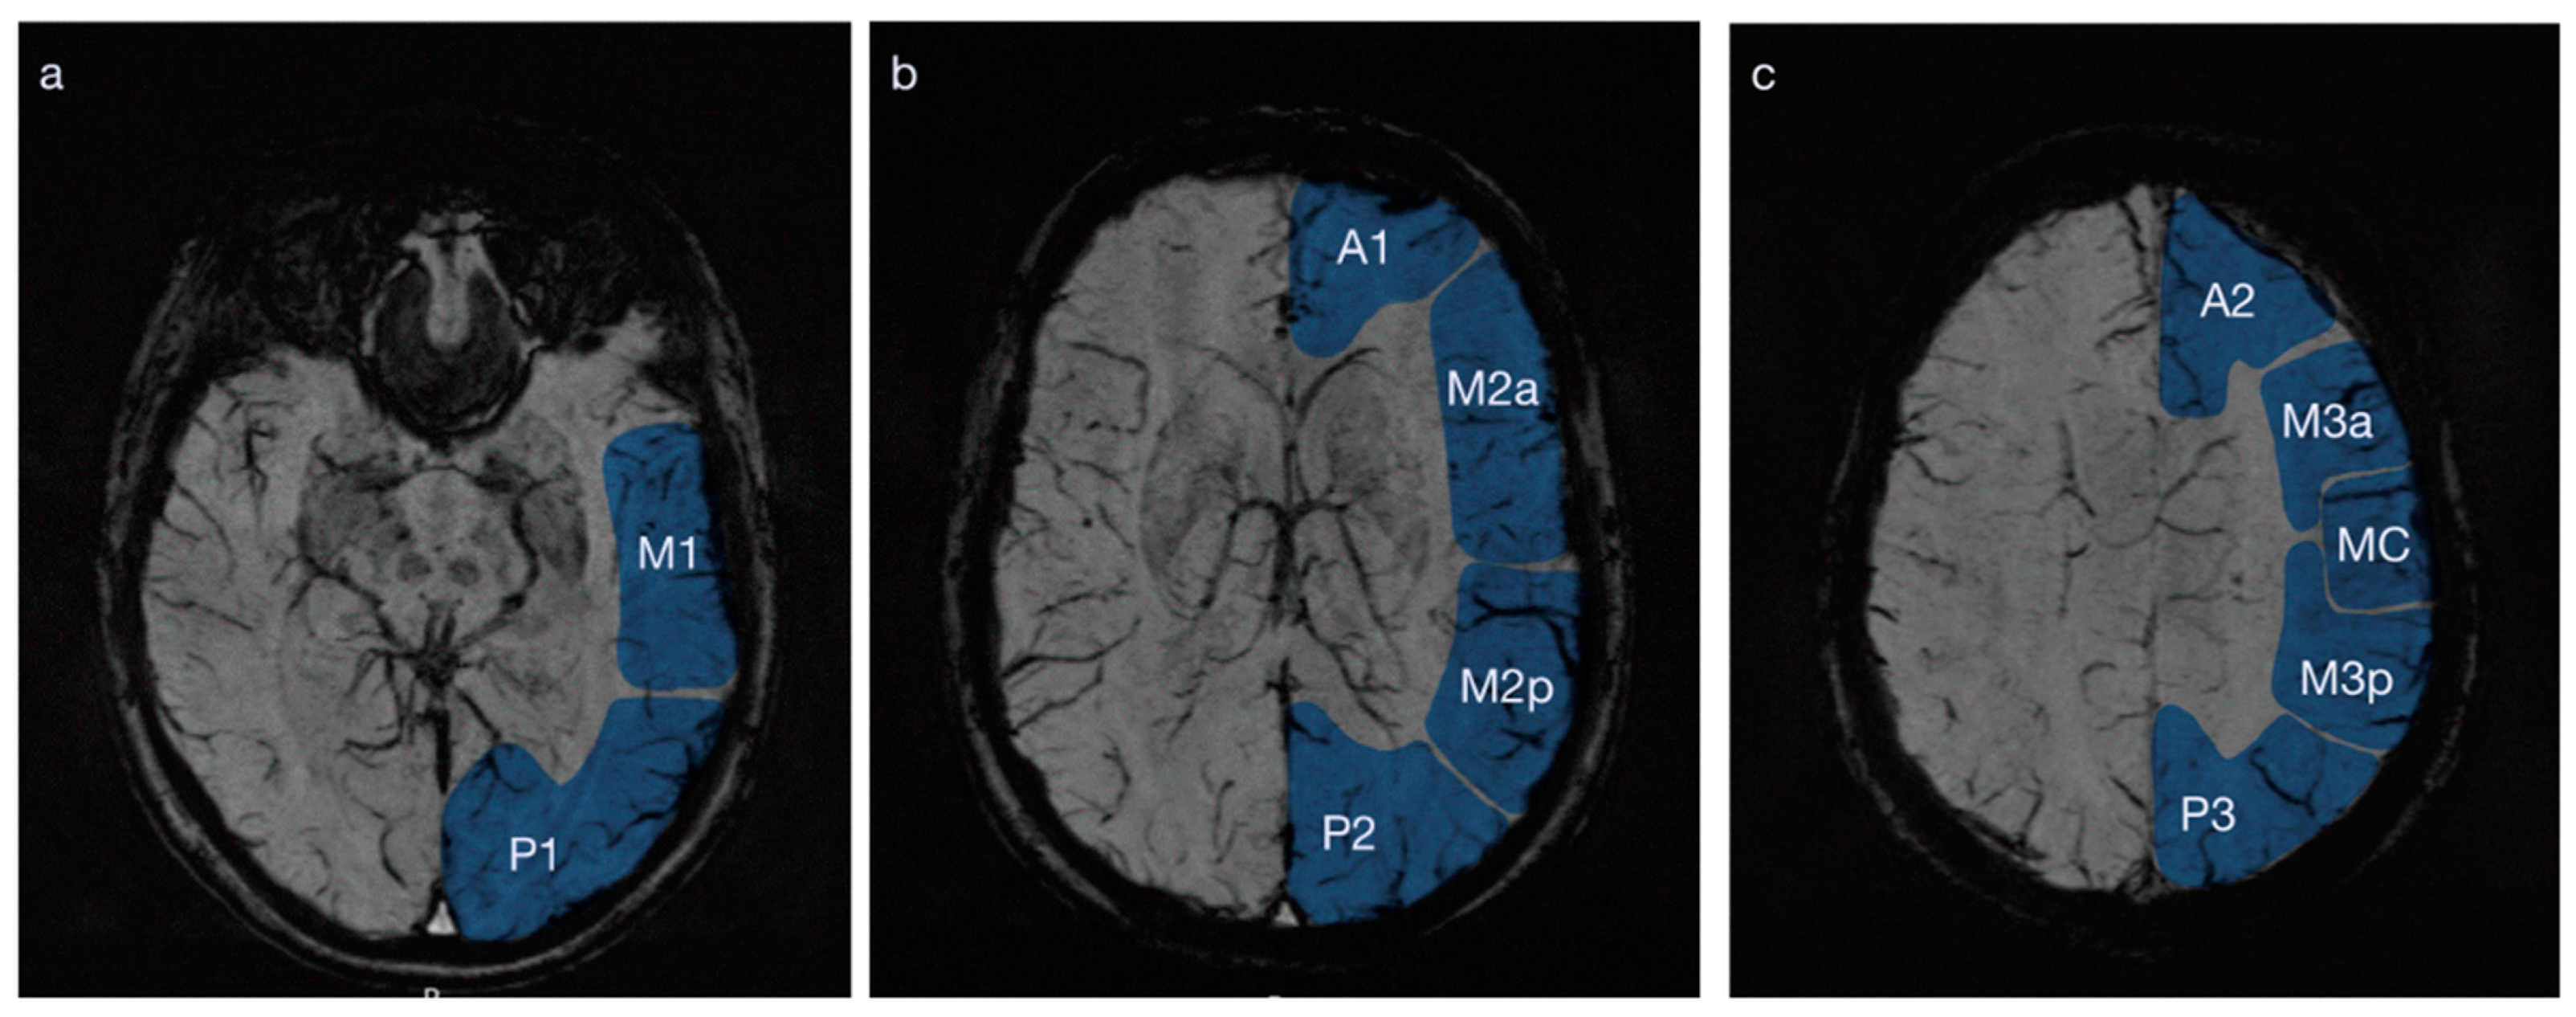

Figure 2.

Distribution of susceptibility weighted imaging (SWI) changes (created in BioRender.com). The percentages depict the frequencies of the SWI changes during acute migraine aura. The SWI changes were more frequent in the posterior regions, with a clear posterior to anterior gradient. There was a left-hemispheric dominance, likely due to a selection of patients with left-hemispheric symptoms, which, being more severe (e.g., aphasia), are more likely to be worked-up in the emergency setting.

All 18 patients with visual disturbances had SWI changes in the posterior region (details visualized in Figure 2). Of the 12 patients with speech disturbance, all 12 had SWI-changes in the Ma region, 5/12 (42%) had changes in the A region and none had changes in the MC region. Of the 10 patients with sensory disturbance, all had changes in the M region, 6 (60%) had changes in the A region and 2 (20%) had changes in the MC region. Of the three patients with motor symptoms, all patients had changes in the M region, two (67%) had changes in the A region and one (33%) had changes in the MC region. The distribution of symptoms for each region is given in Table 1.

With each added area with PFVs, the proportions of affected patients declined (see Table 2), e.g., for patients with visual symptoms with PFVs in the left hemisphere, there were 10/12 (56%) with PFVs in the P2 + M2p areas, 7/12 (59%) in the P2 + M2p + M2a and 2/12 (11%) in the P2 + M2p + M2a + A1 areas. This pattern of distribution was observed for all symptoms and both hemispheres.